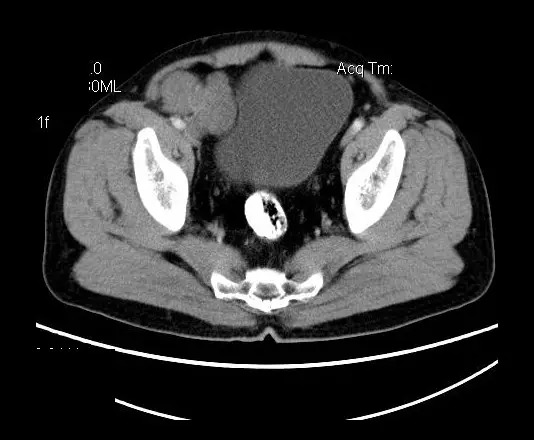

【影像表现】

盆腔右前侧及邻近腹股沟区可见多发大小不等的聚集生长的结节影,病灶呈软组织密度,边缘尚规整,分界尚清,增强扫描可见不均匀强化。膀胱局部受压,盆腔未见明显肿大淋巴结影。

“盆腔”多发性神经鞘瘤